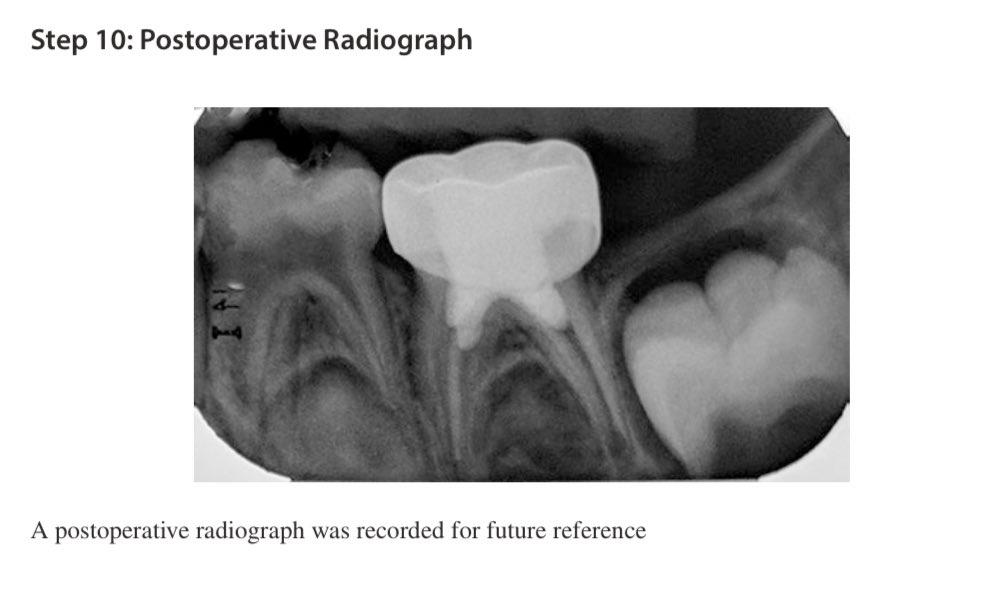

خذ اشعة بعد عشان تقييم نفسك وتصير بالسجل عندك